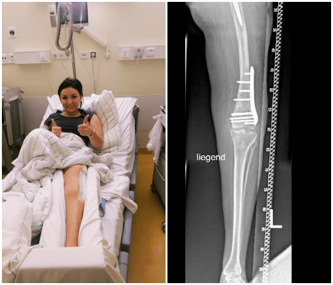

Jestem już po operacji!

Pierwszy etap zakończony! To wszystko dzięki Wam! Fundacji Siepomaga i Wszystkim, którzy pomogli spełnić moje marzenie! Operacja odbyła się 25 stycznia w Berlinie, cały zespół lekarzy bardzo się napracował, z prof. Perką na czele przeprowadził rekonstrukcję mojej nogi, która trwała aż 5 godzin i zakończyła się sukcesem! Dla lepszego efektu mam włożoną także endoprotezę lewego biodra. Nóżka naprawiona!! Piękna!! Prosta!! Urosłam 10 cm! Wyprostowana i szczęśliwa wróciłam do domu! Prof. Perka po przeprowadzonej operacji powiedział, że nie widział tak poprzekręcanej nogi… i nie może sobie wyobrazić, jak chodziłam na niej tyle lat. Jestem taka szczęśliwa, że daliście mi tą szansę! Odzyskałam nadzieję, że może być lepiej, że się da, że można żyć bez bólu. Dziękuje Wam za nową nogę i nowe życie! :)